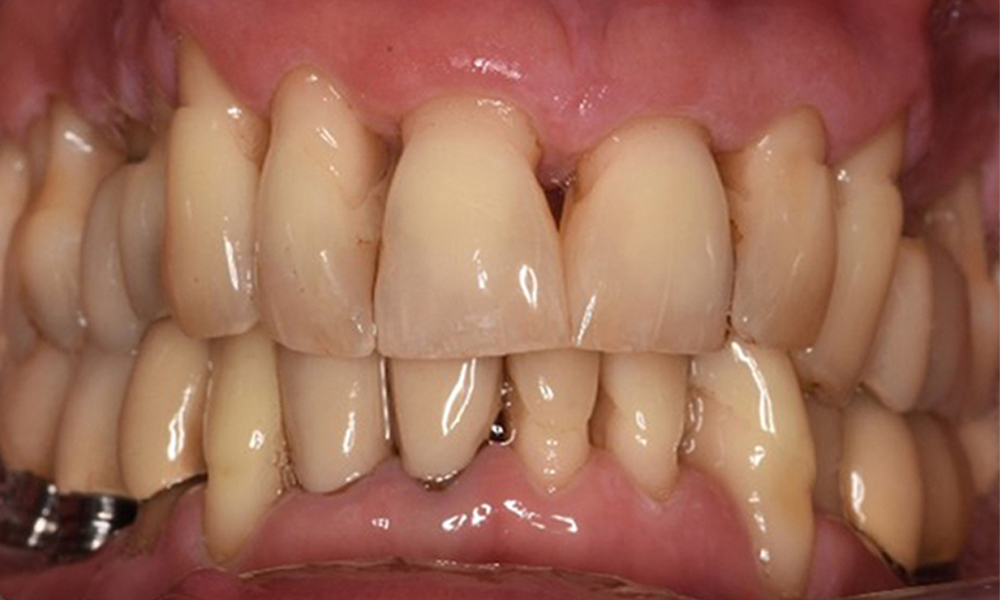

A 52-year-old patient presents at a preventive care session. The patient has no systemic disease and is not taking any medication. He has had various dental treatments and also has two active carious lesions. In addition, the patient has four implants (2nd, 3rd and 4th quadrants). He is revealed to have early periodontal disease (stage IV, grade B). His periodontal condition is stable; a probing depth of Probing depths (ST) of 5 mm is only evident at the implant in region 36. Gingivitis is also identified.

Oral hygiene and patient compliance are very good (see picture “front view”). All that is required is repeat instruction and motivation to maintain oral hygiene behaviour.